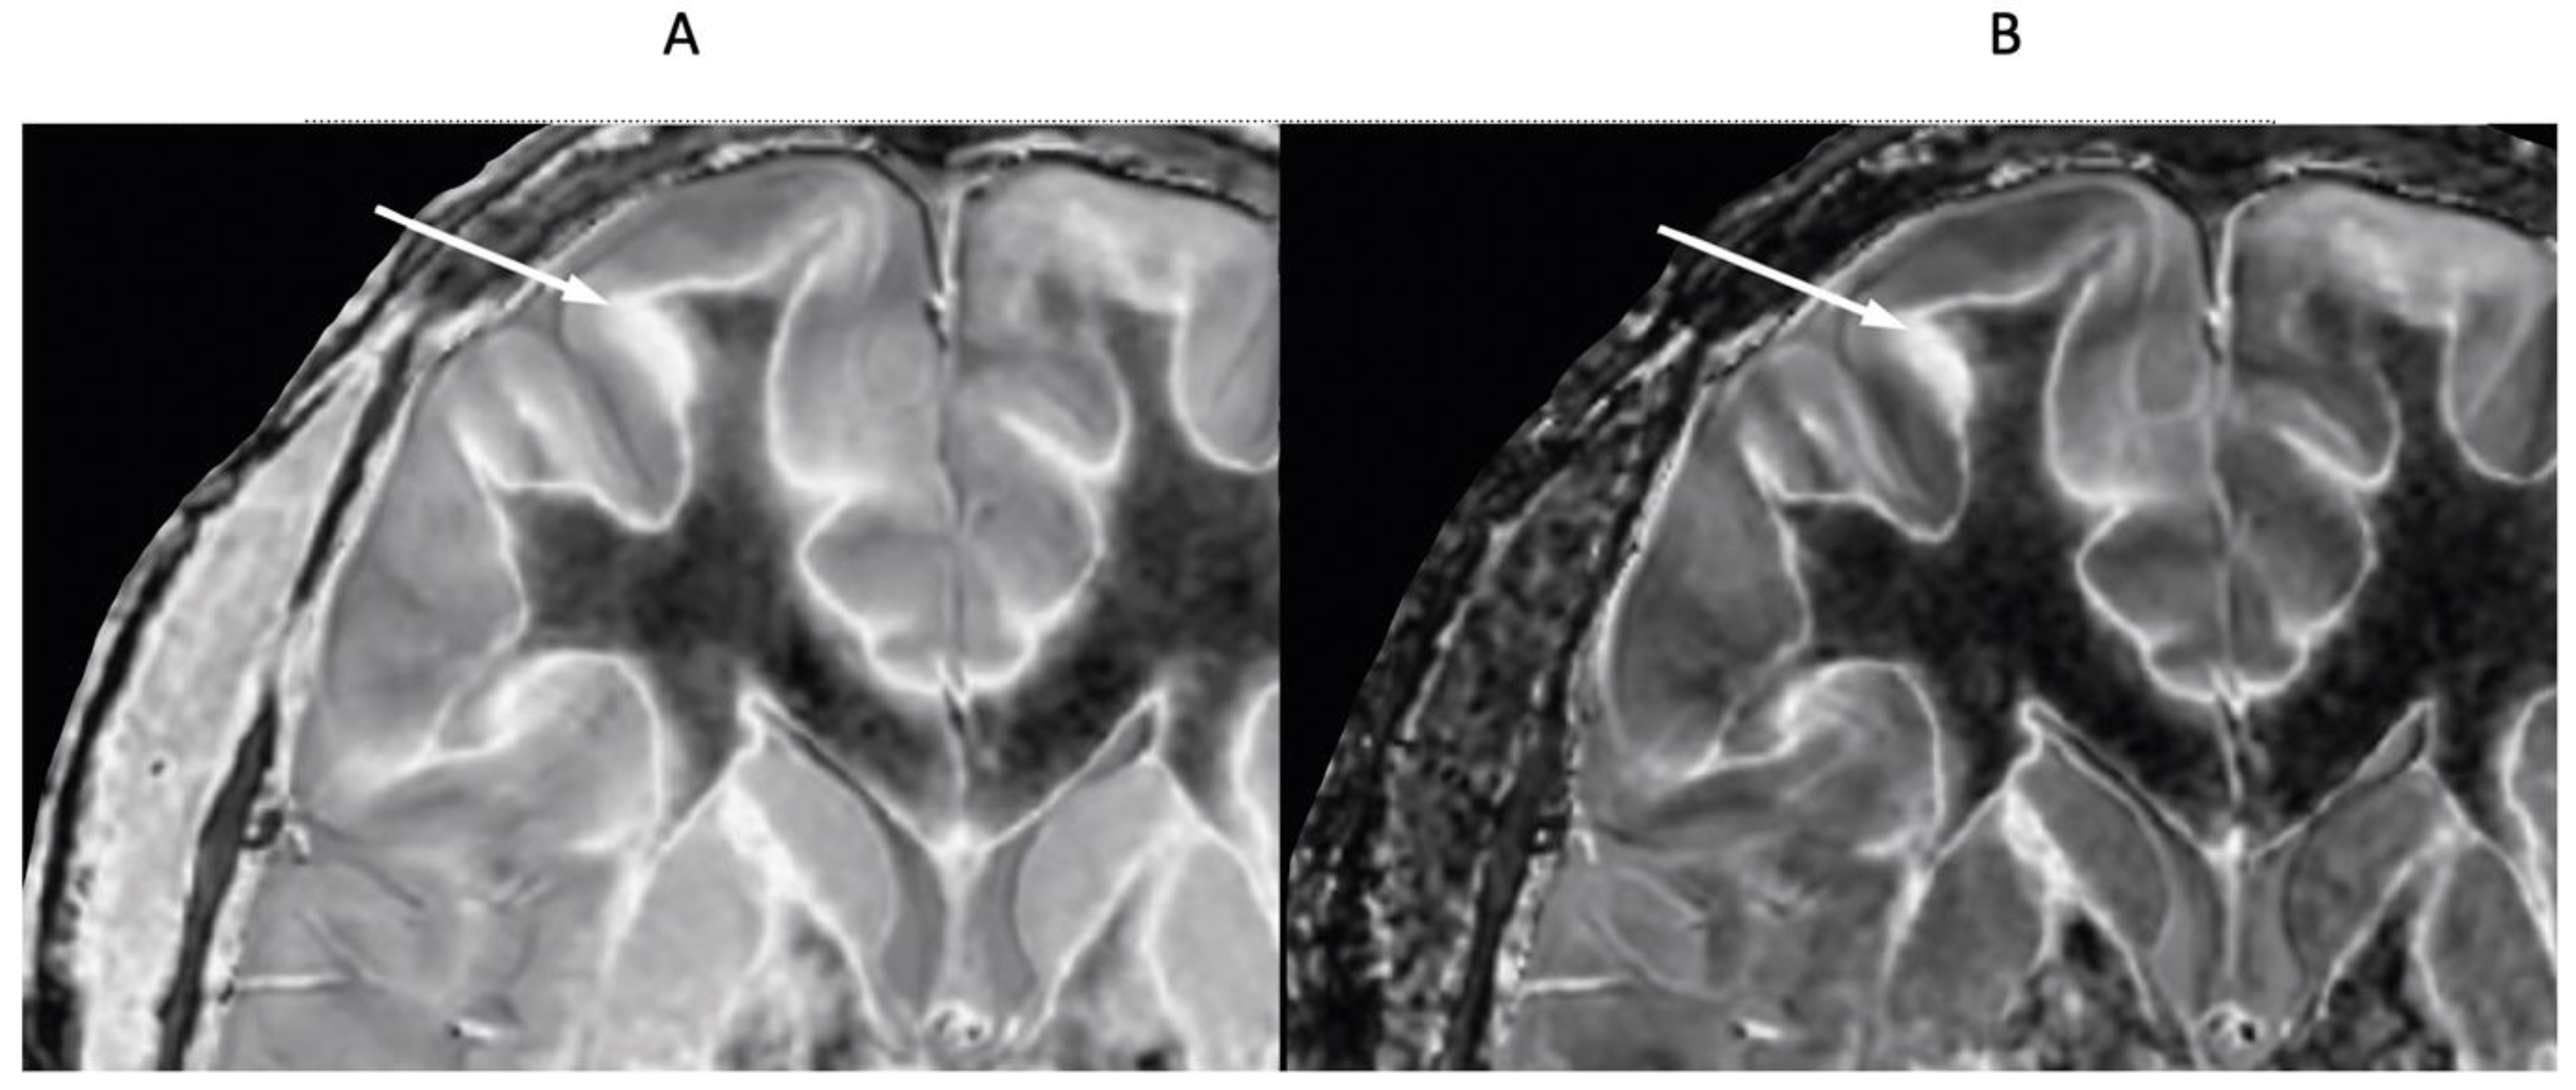

4. Illustrative Cases

5.2.1. Whiteout Sign

5.2.2. Grayout Signs